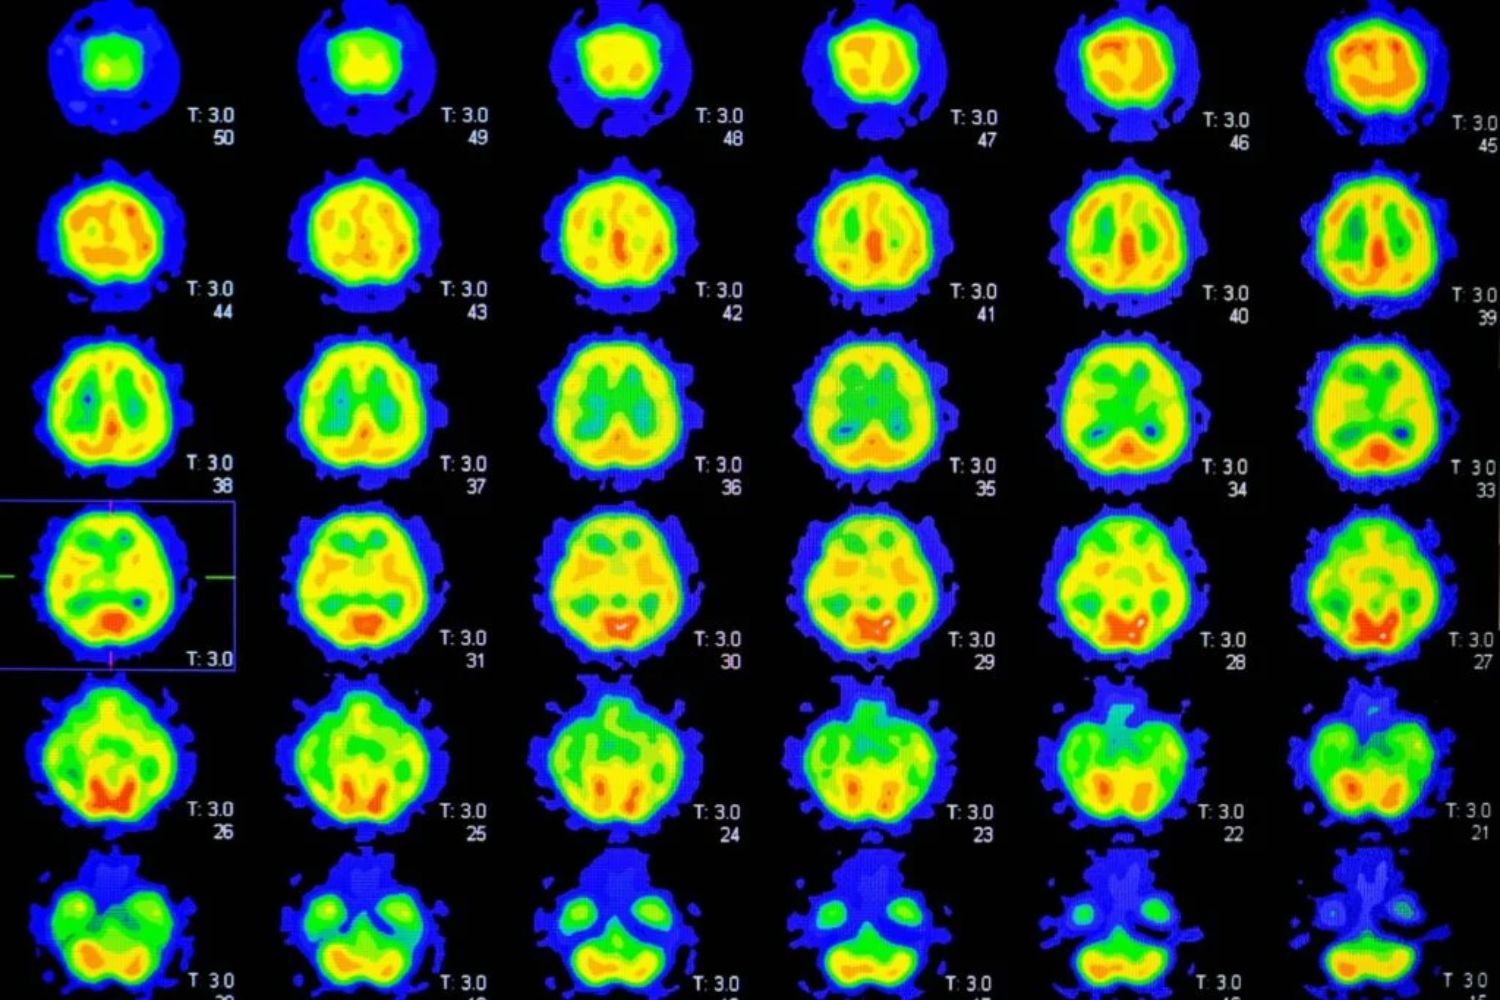

Diese Ablagerungen beginnen sich bereits Jahre oder Jahrzehnte vor den ersten Symptomen zu bilden. Eine spezielle PET-Bildgebung kann diese Anhäufung erkennen. Auch wenn ein Scan allein Alzheimer nicht bestätigt oder ausschließt, ist er ein wichtiges Instrument zur Risikoabschätzung und Verlaufskontrolle.